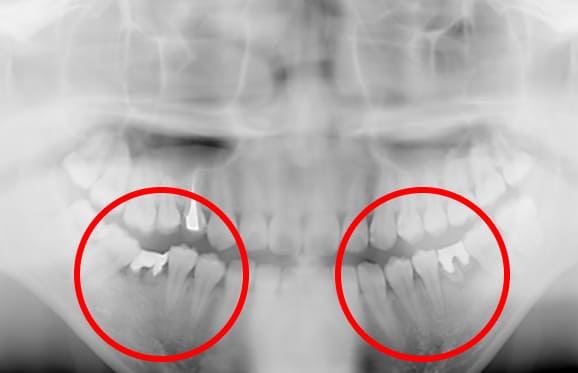

● C4を超え歯根までの虫歯を抜歯、親知らずを利用して歯並び全体を整えた症例

藤沢デンタルオフィスの虫歯や破折で抜歯後の部分矯正